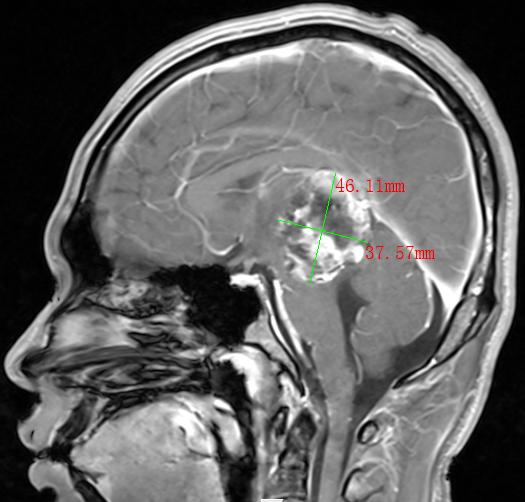

2022年,30多岁的张先生和40岁岁的李先生,均出现神志模糊或不清,并有反复癫痫发作的情况,经过当地医院检查,张先生和李先生分别诊断为松果体肿瘤、间变型星形细胞瘤术后复发并多发种植转移,两人颅内肿瘤直径分别达4.0cm和9.8cm。由于两人颅内肿瘤太大,辗转多家医院求医未果,正当两家人要放弃的时候,听朋友介绍瑞康医院射波刀治疗恶性肿瘤的效果非常不错,两家人怀着试一试的心态来到瑞康医院肿瘤科一区。

松果体区肿瘤MRI影像